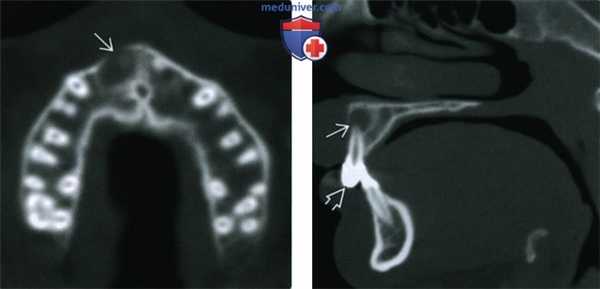

3. КТ при боковой периодонтальной кисте:

• КЛКТ:

о С щечной стороны от корней прорезавшегося зуба

о Иногда со вздутием щечной кортикальной пластинки или перфорацией